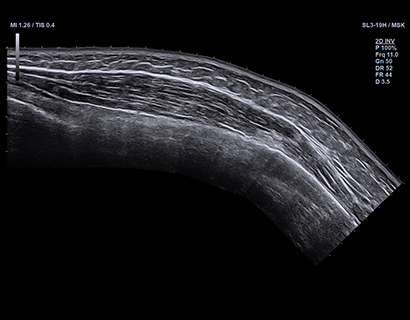

SL3-19H

X+ Crystal Signature™ linear transducer(3~19MHz)

Application:

MSK, Vascular, Small Parts, Breast, TCD, Abdomen, Pediatric, Gynecology, Obstetrics, EM